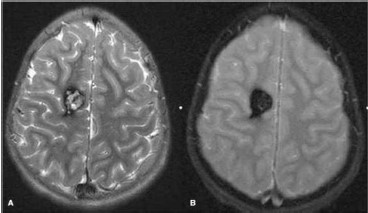

Paciente do sexo feminino, 40 anos de idade, comparece ao ambulatório de neurologia, referindo ter apresento, há 5 dias, crise convulsiva tônico-clônica, com início focal no membro inferior esquerdo e generalização secundária. Apresentou a ressonância magnética a seguir.

A sua primeira hipótese da etiologia desse caso é: